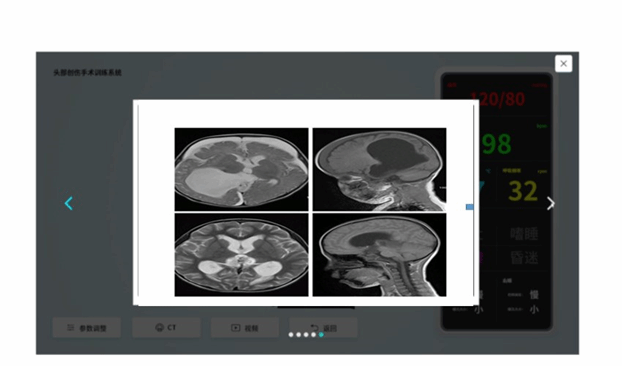

图1 脑积水影像学图示意

学生可通过鼠标和键盘操作,自由进入到 3D 虚拟的手术室,点开某个患者的病史及影像学,进行影像读片,选择是否需要手术干预。(此点考查脑室引流的适应症、禁忌症。)